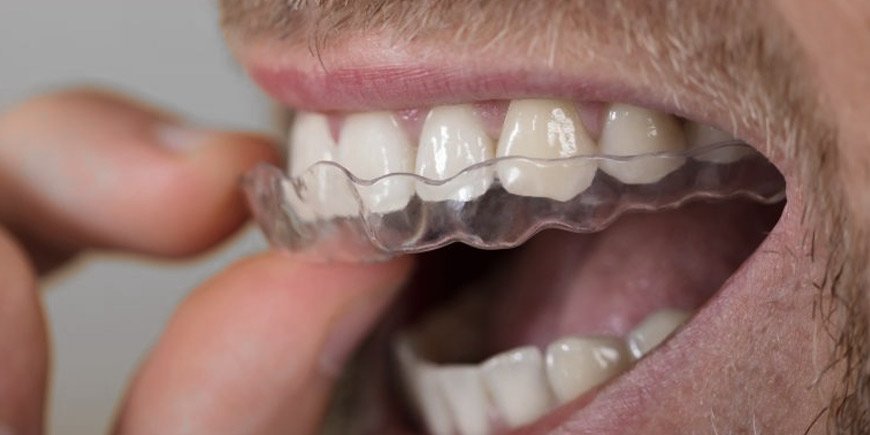

Guarda desprogramador

Dispositivo que se utiliza con el objetivo de relajar los musculos de la masticación, y desprogramar la articulación temporomandibular.